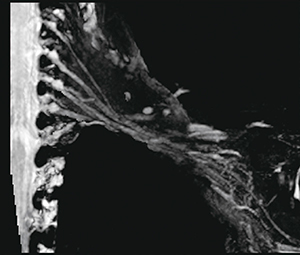

今回は耳下腺内顔面神経について紹介したが,ほかの部位でも管状に神経が描出されていれば,この方法で全体像の描出が可能となる。1例として腕神経叢を提示する(図5)。

図5 腕神経叢 |